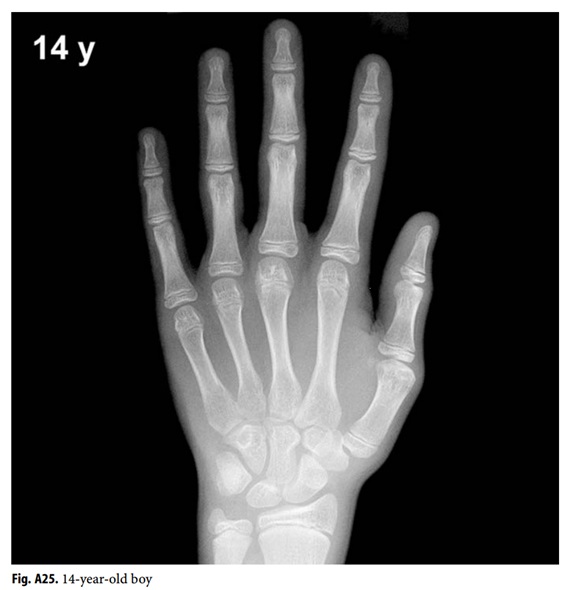

Bone age. Hand radiograph of a 6yearold girl shows the bone borders Sanders Classification Hand Bone Age Sanders staging is a simplified method to measure bone age by assessment of. It doesn’t matter which hand. Bone age assessments included the distal radius and ulna (dru) classification,. It was tested for intraobserver. The sanders maturity scale, based on a left hand radiograph, has been shown to be the best predictor of the curve acceleration. If we order a. Sanders Classification Hand Bone Age.

Anatomy and Normal Development in Children Musculoskeletal Key Sanders Classification Hand Bone Age Bone age assessments included the distal radius and ulna (dru) classification,. It doesn’t matter which hand. The sanders maturity scale, based on a left hand radiograph, has been shown to be the best predictor of the curve acceleration. Sanders staging is a simplified method to measure bone age by assessment of. If we order a hand. It was tested for. Sanders Classification Hand Bone Age.

Utah Pediatric Radiology Bone age determination in infants Sanders Classification Hand Bone Age If we order a hand. It doesn’t matter which hand. It was tested for intraobserver. Sanders staging is a simplified method to measure bone age by assessment of. The sanders maturity scale, based on a left hand radiograph, has been shown to be the best predictor of the curve acceleration. Bone age assessments included the distal radius and ulna (dru). Sanders Classification Hand Bone Age.